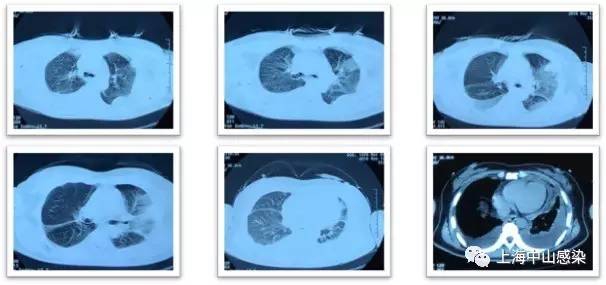

6月14日复查胸部CT2:肺炎稍吸收,但双侧胸腔积液更加明显

CT1.jpg